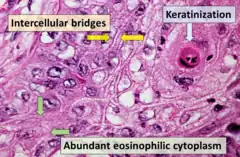

- Squamous cell carcinoma

- Refers to a carcinoma with observable features and characteristics indicative of squamous differentiation (intercellular bridges, keratinization, squamous pearls).